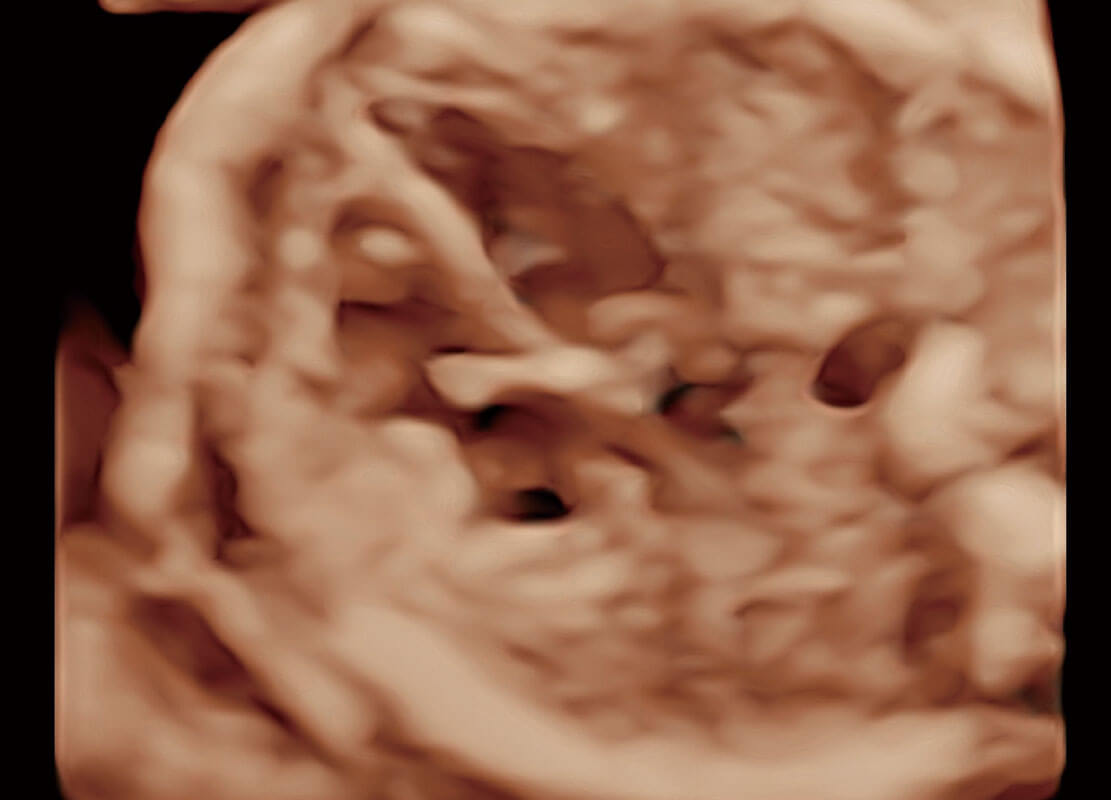

高分辨率容积成像-早孕胎儿

P60搭载一系列胎儿心脏成像技术,实现精细的胎儿心脏评估。

胎心容积成像